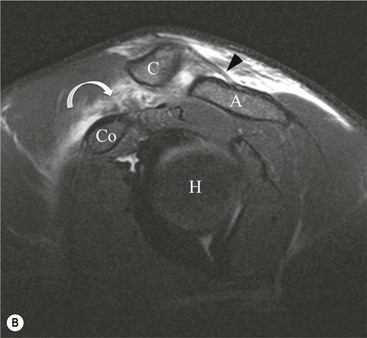

The primary sign of a rotator cuff FTT is a focal deficiency of the tendon (Figs. 46-4 and 46-5). This nearly always occurs at the tendon insertion on the tuberosity. The margins of the tear are best delineated when there is fluid within the tendon defect. Secondary signs of an FTT include the presence of fluid in both the GHJ and SAB, and flattening or concavity of the subacromial fat plane.

PTTs are less reliably demonstrated by both MRI and US, and it may be difficult to differentiate tendinopathy from partial tears. Focal clefts, tears, or tendon thinning affecting the articular margin of the footprint of the tuberosity are most common (Figs. 46-6 and 46-7). Tendon thickening is not always present. It is important not to mistake magic angle phenomenon on short TE MR sequences or anisotropy on US as evidence of tendinopathy.2